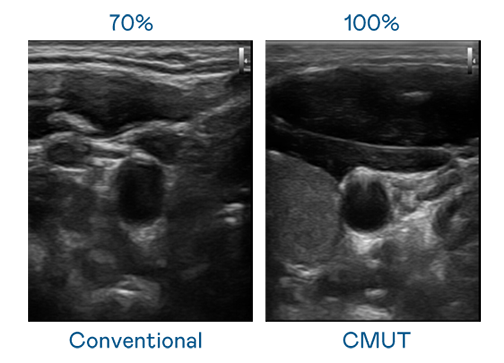

CMUT 技術是一種用電容式微機電元件來產生超音波訊號的技術。與傳統 PZT 壓電式技術相比,CMUT 頻寬增加 30%,更寬頻的超音波訊號讓影像解析度大幅提升,是實現高影像品質醫療超音波掃描、促進精準醫療發展的關鍵技術。

超音波影像的解析度高低,首先取決於探頭能發出的訊號頻寬。圣淘沙 CMUT 可提供高清晰的超音波訊號,提供高頻寬、高靈敏度、影像紋理細節更高的超音波影像,協助醫護人員縮短影像判讀時間及利用精準的醫療影像進行診斷。